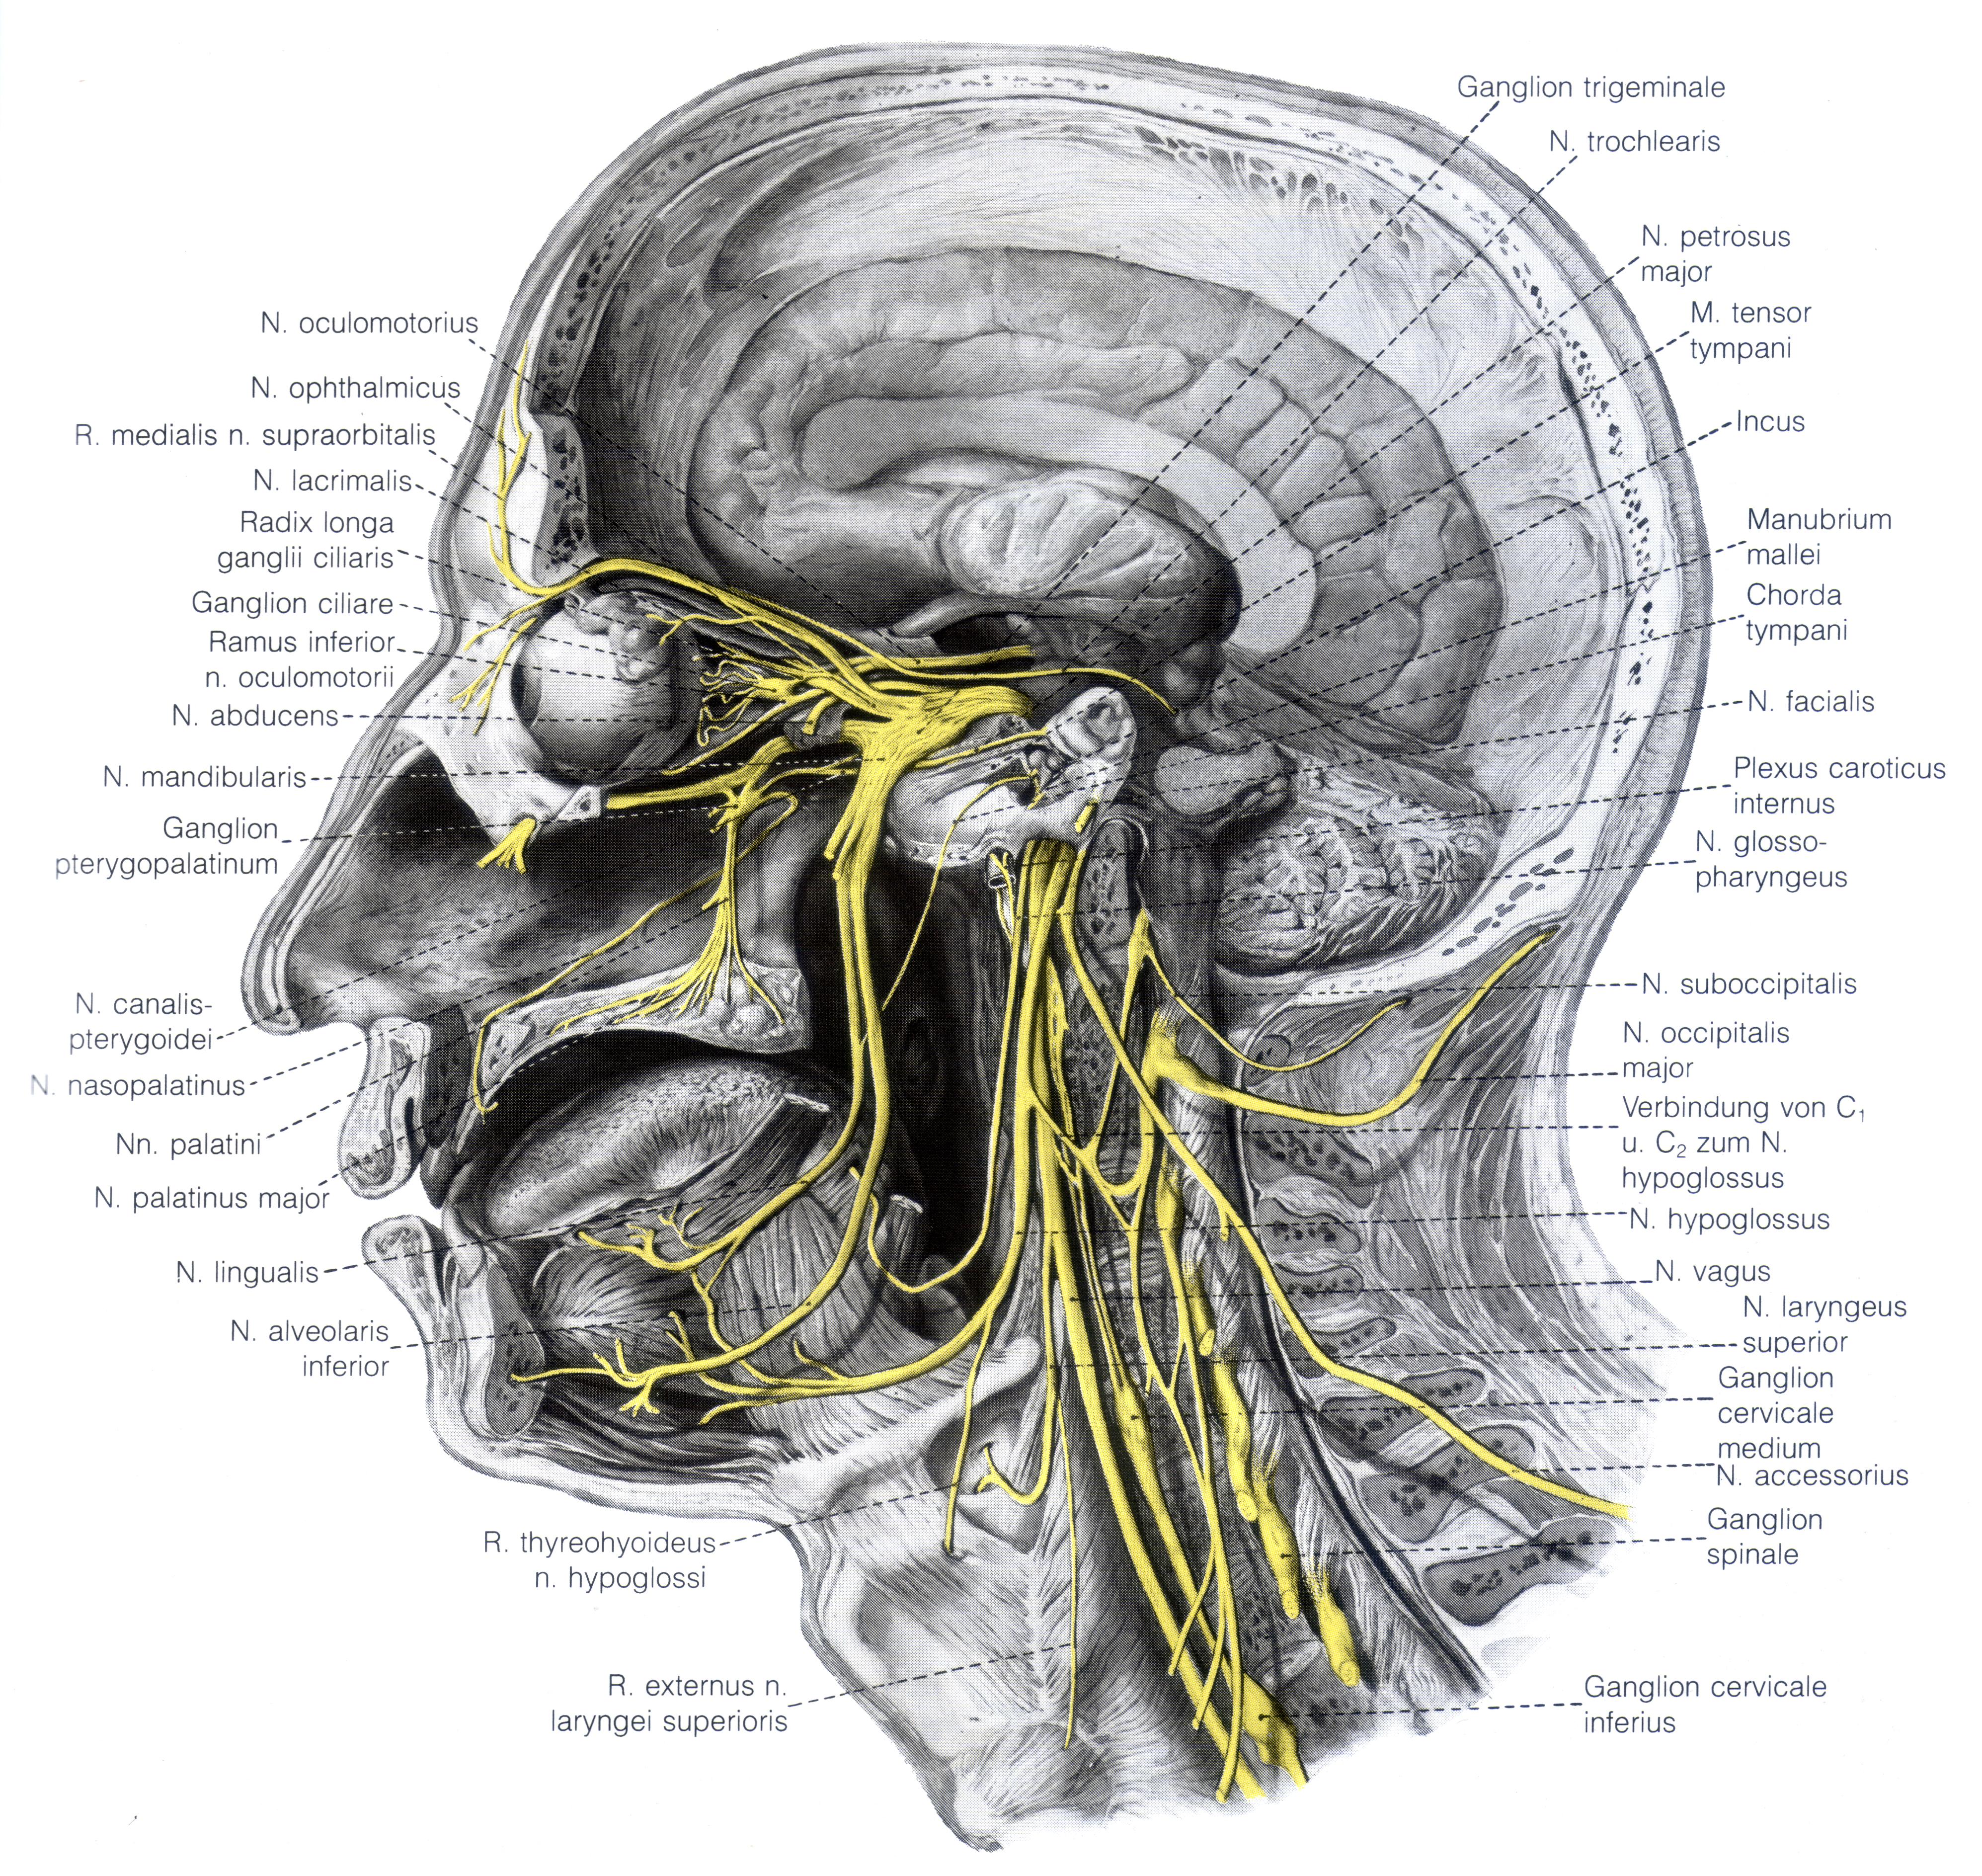

Анатомия внутренней яремной вены: КТ изображения

Раздел: Другие животные